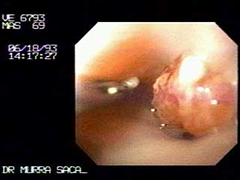

Foto de vídeo endoscopia:

Cáncer Gástrico en etapa temprana, se observa una nodulacion hacia la izquierda y una pequeña ulceración da la impresión de esta lesión temprana se ha degenerado de un pólipo, la teoría adenoma carcinoma.

La lesión midió tres milímetros en el estudio histologico. -